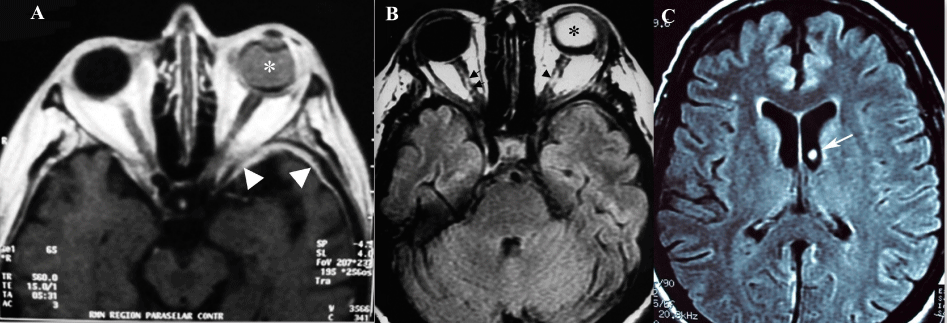

| Figure 1: (A) T1 weighted axial image with contrast shows: (a) hyperintense signal in the left eye consistent with the silicone oil placed for the retinal detachment (white asterisk), b) meningeal enhancement in the left temporal pole region (white arrowheads). (B) MRI FLAIR image shows: (a) hyperintense signal within vitreal cavity representing silicone oil in the left eye (black asterisk), and (b) hyperintense signal in the optic nerves on the right (double black arrows) and left (single black arrowhead), indicating inflammation and/or edema. (C) Round hyperintense signal in the left lateral ventricle with the same intensity as the contents of the left eye consistent with silicone oil (white arrow). |